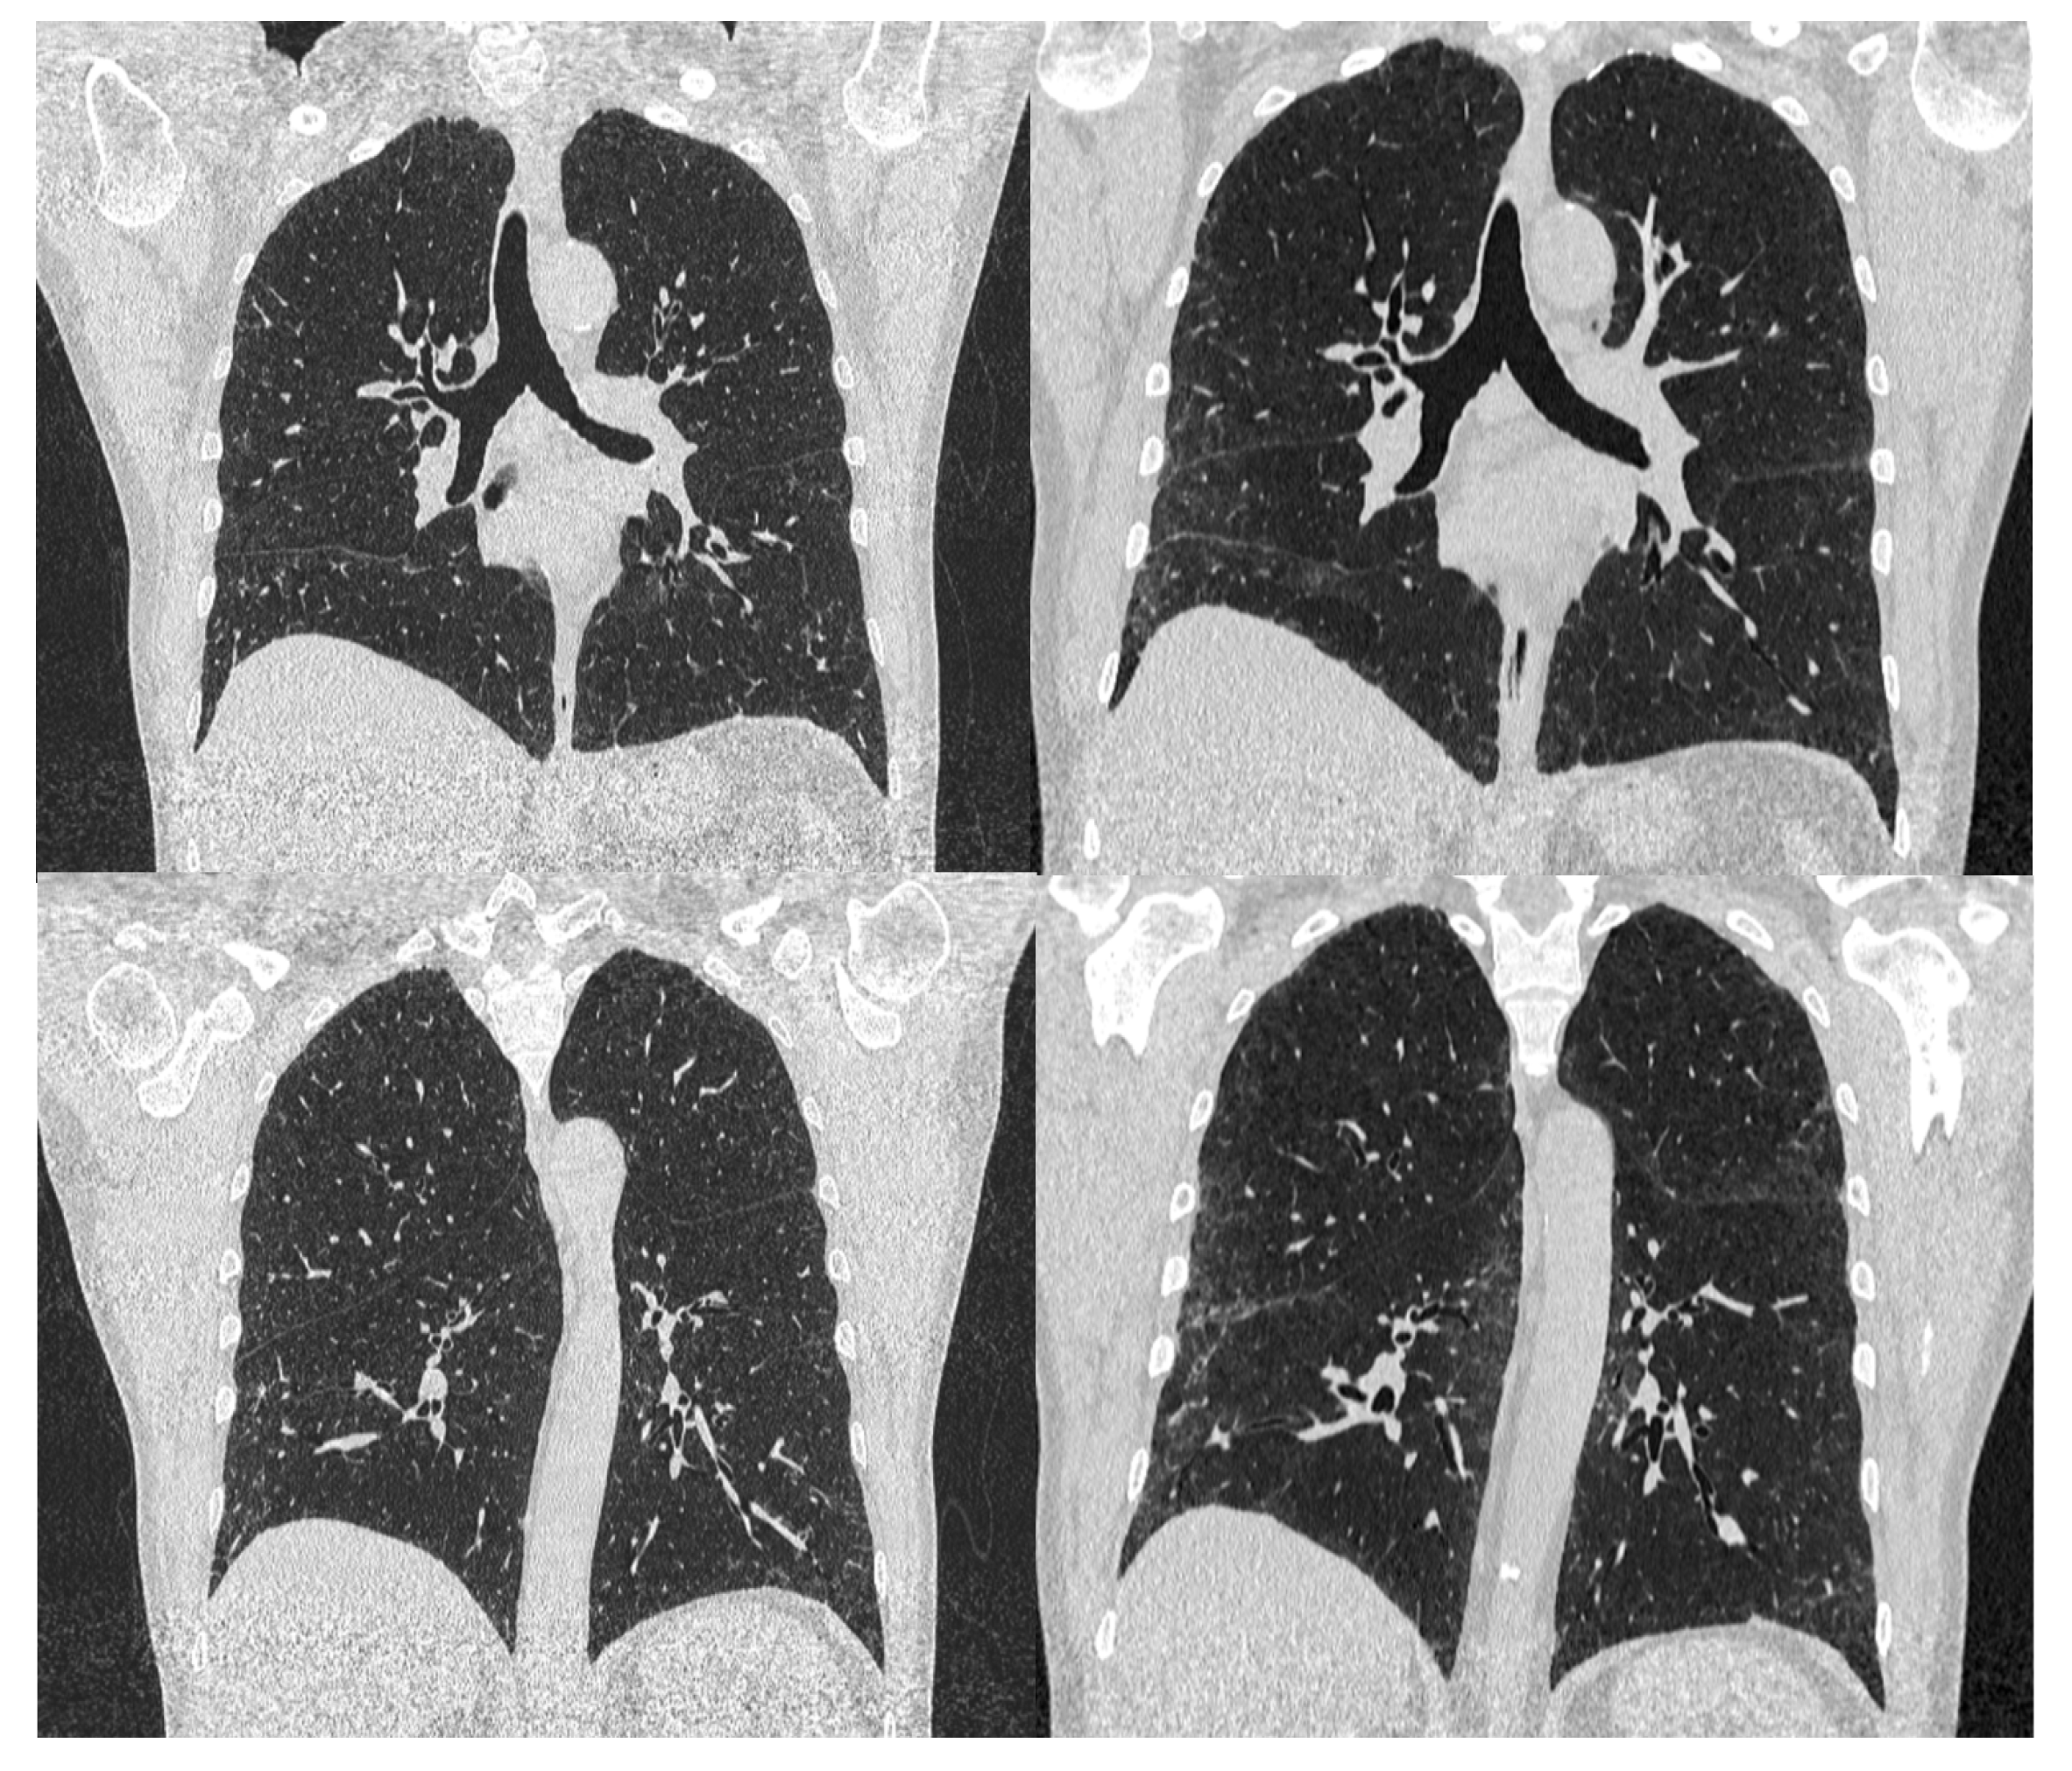

2. Case Report